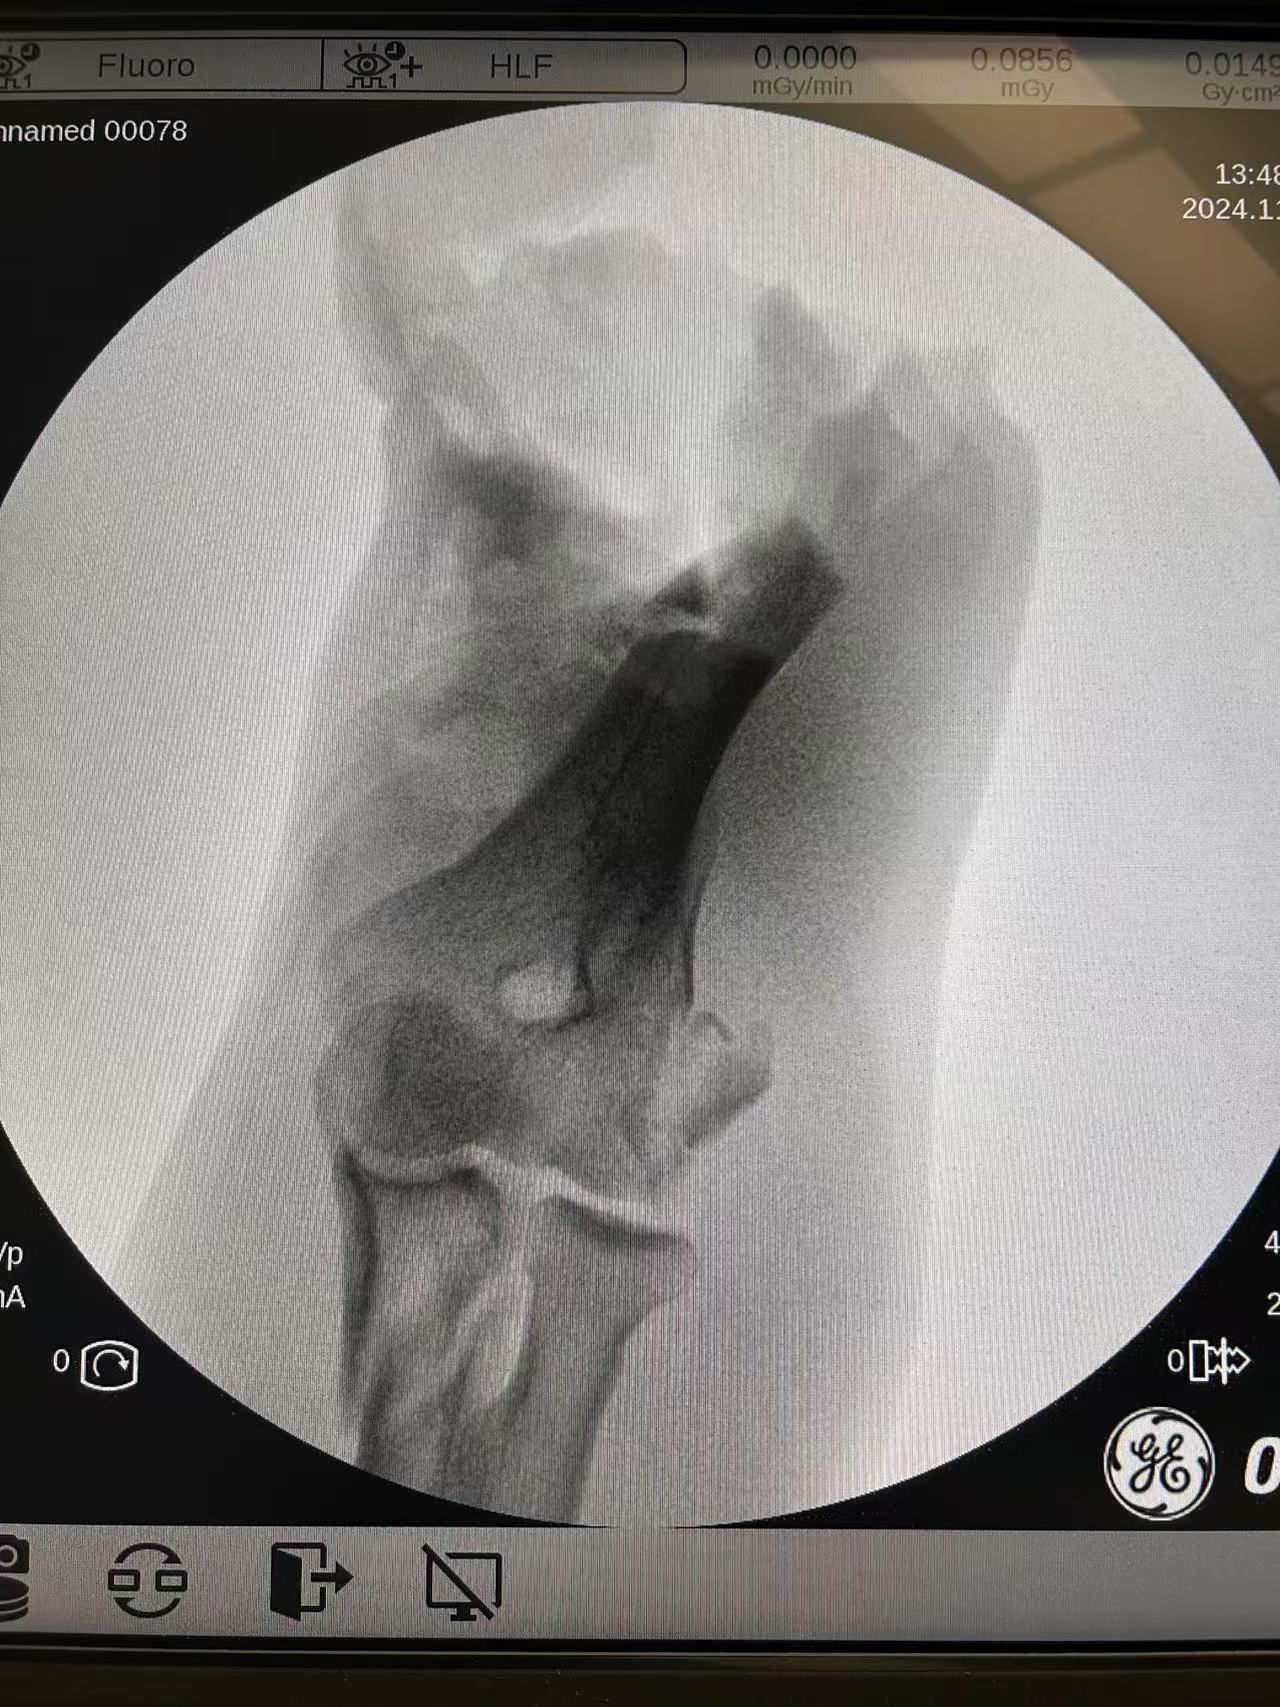

在周庞虎主任指导下,洪山院区骨外科胡锐、江泽文、李潇等手术组医生首先将离断的患肢彻底清创,使用外固定支架稳定骨折断端,并在显微镜下用细如发丝的显微缝合线吻合了右侧肱动脉、3根静脉和上肢三大神经,并依次缝合断裂肌腱及肌肉组织。连续手术6个小时后,此前完全离断的右上肢被成功“接”了回去。

手术刚完成,患者右上肢血管再通后,皮肤颜色成功转红。在手术室门口焦急等待的患者家属,目睹断肢被接回且生命体征稳定后,由衷表达了对医护人员的感谢。